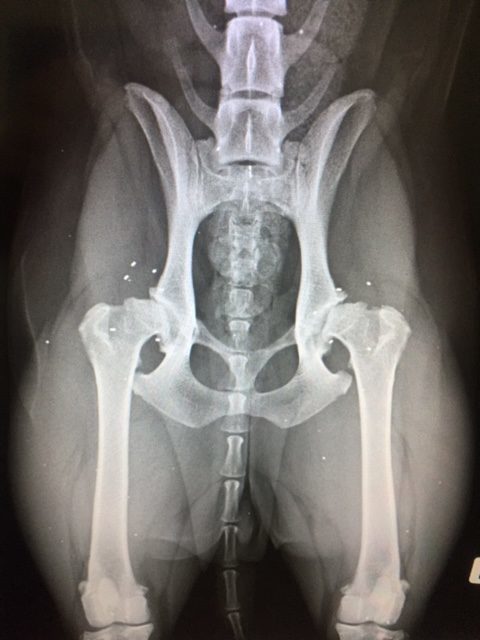

Fallbeispiel 2: Emma, Golden Retriever, 4 Jahre alt

Emma litt an einer schweren Hüftgelenksdysplasie (HD). Infolge der anhaltenden Fehlbelastung entwickelte sich eine starke Arthrose am Ellenbogen. Sie erhielt die Goldakupunktur an den Hüften und am Ellbogen. Seitdem läuft sie schmerzfrei und ist eine sehr aktive und verspielte Hündin.